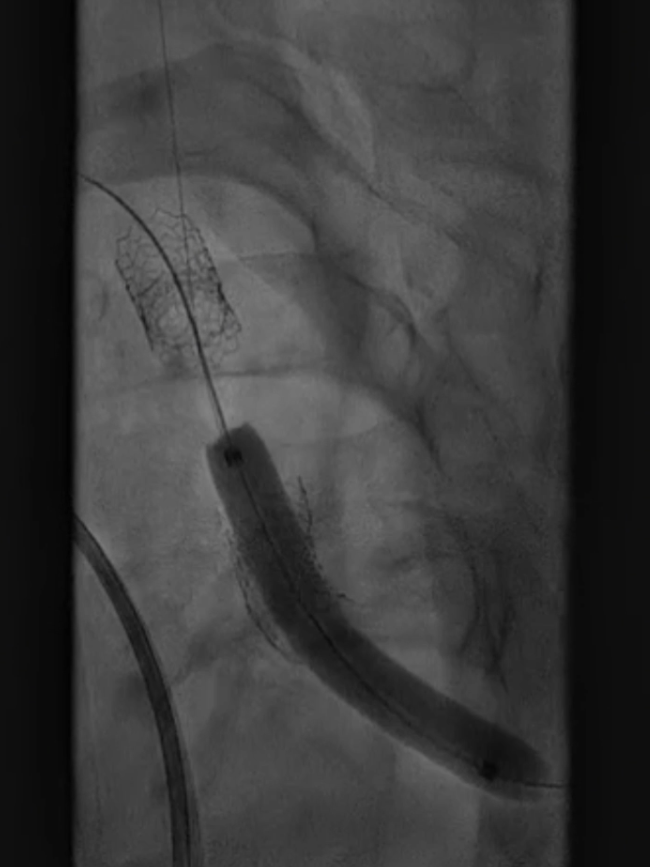

支架置入:通过“球囊带鞘”技术跟进长鞘至支架远端,采用同轴双导丝技术送入VBX8×29mm球扩覆膜支架,多角度造影定位后释放。

撤球囊时更进长鞘

至支架远端

同轴双导丝技术送入

VBX 8*29mm球扩覆膜

支架反复造影定位

释放支架